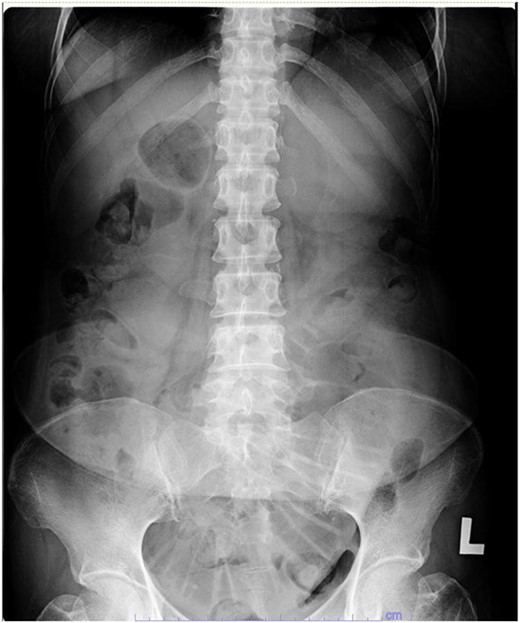

Her abdominal x-ray showed a dilated small bowel with a most likely transition point at the ileum and a collapsed large bowel (Fig. 1). Computed tomography (CT) of the abdomen showed an intussusception with the transition point at the proximal ileum with mesenteric invagination (Figs. 2 and 3).

Abdominal x-ray showing a dilated small bowel with valvulae conniventes.